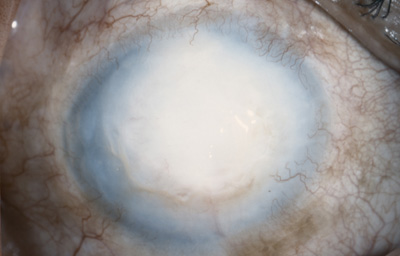

Paciente masculino de 34 años, agricultor; 20 meses antes de la consulta sufrió picadura en el Ojo Derecho de avispa amarilla “la llaman vaquera” en Saravena. Operado con ltrante a los 4 meses.- Se aplica Optimol

Al examen OD Leucoma denso central con grandes bullas y vaso estromal profundo que penetra a las 6; notable engrosamiento corneal, ( Fistula interna en córnea?) y no panus vascular periférico, midriasis paralítica, goniosinequia en 360o ?.- catarata intumescente, cicatriz quirúrgica superior, Tono digital medio (Foto No 19)

Foto 19 - Leucoma denso con bullas y vaso estromal profundo a las 6

Conducta: Se realiza Queratoplastia penetrante 8.2 mm + Sinequiotomía angular con Viscoelástico + Extracapsular +LIO en OD. En el postoperatorio, injerto trasparente con hipertensión ocular controlada con medicación, gran excavación del Nervio Optico

A los 151 dias de postoperatorio, se aprecia edema del injerto.- Se inició tratamiento; a los 9 meses de postoperatorio se retiraron las suturas, manteniendo el tto antihipertensivo.- EL PACIENTE NO REGRESO